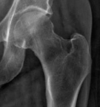

Extracapsular NOF

Subcapital fracture (intracapsular)